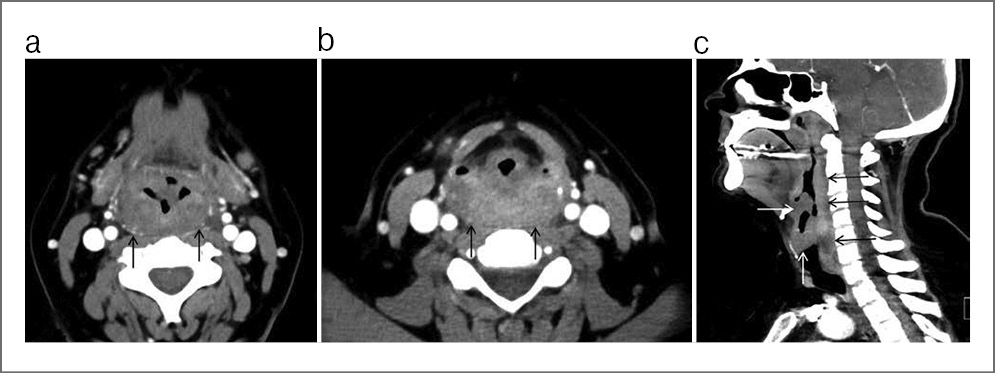

Пациент предоставил заключение врача-инфекциониста, данных о наличии герпесвирусной инфекции, инфекции, вызываемой вирусом Эпштейна–Барр, и цитомегаловирусной инфекции не получено. Пациенту назначена компьютерная и магнитно-резонансная томография околоносовых пазух для определения распространения патологического процесса, а также исключения инвазии в смежные анатомические области (рис. 2, 3). В предоперационном периоде под контролем эндовидеоскопического оборудования пациенту выполнен забор материала из свода носоглотки, верифицирован диагноз саркоидоза носоглотки (рис. 1, 4).

Рис. 2. Результаты компьютерной томографии околоносовых пазух у пациента с диагнозом саркоидоза носоглотки. Стрелками обозначен патологический процесс.